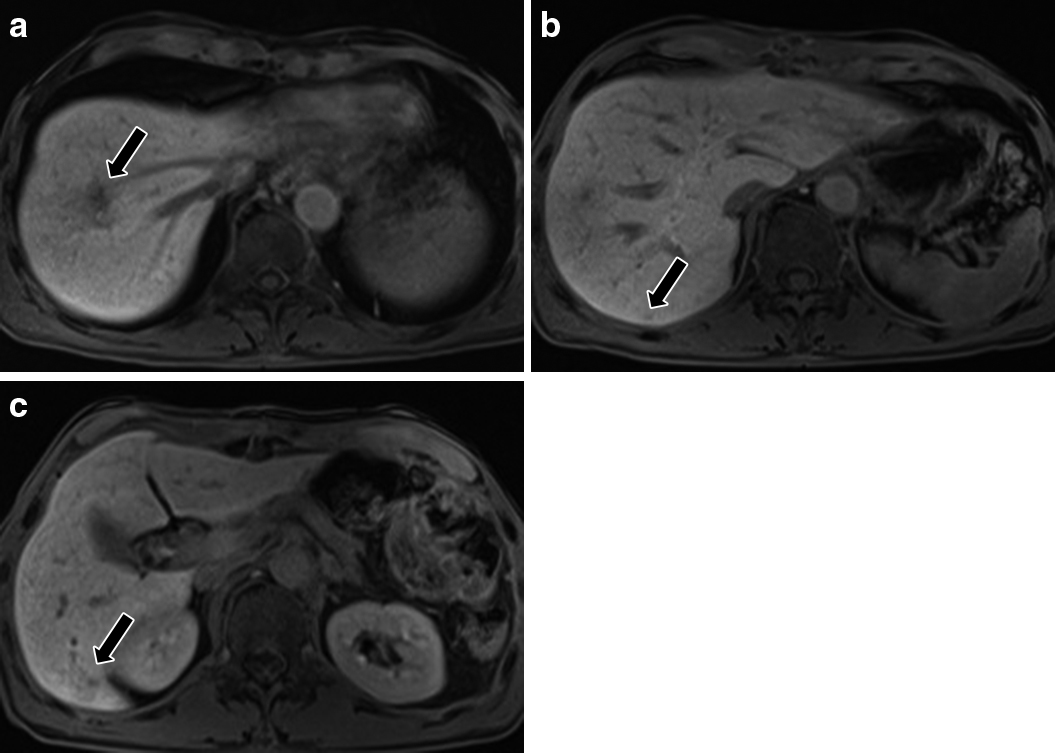

Gd-EOB-DTPA(プリモビスト)MRI所見:SOX療法後,肝細胞相で肝S8の転移巣は径2 cmのlow intensity areaとして描出された.また,S6最頭側と尾側端の転移巣が肝細胞相でlow intensity areaとして描出された.その他の転移巣は指摘困難であり,新規病変は認めなかった(Fig. 3a~c).

Gd-EOB-MRI findings. a–c) After SOX. a) S8 tumor was remarkably reduced to 2 cm in diameter (arrow). The tumors on the b) most cranial side (arrow) and c) caudal edge (arrow) in S6 were demonstrated as a small low-intensity area, although other lesions were invisible.